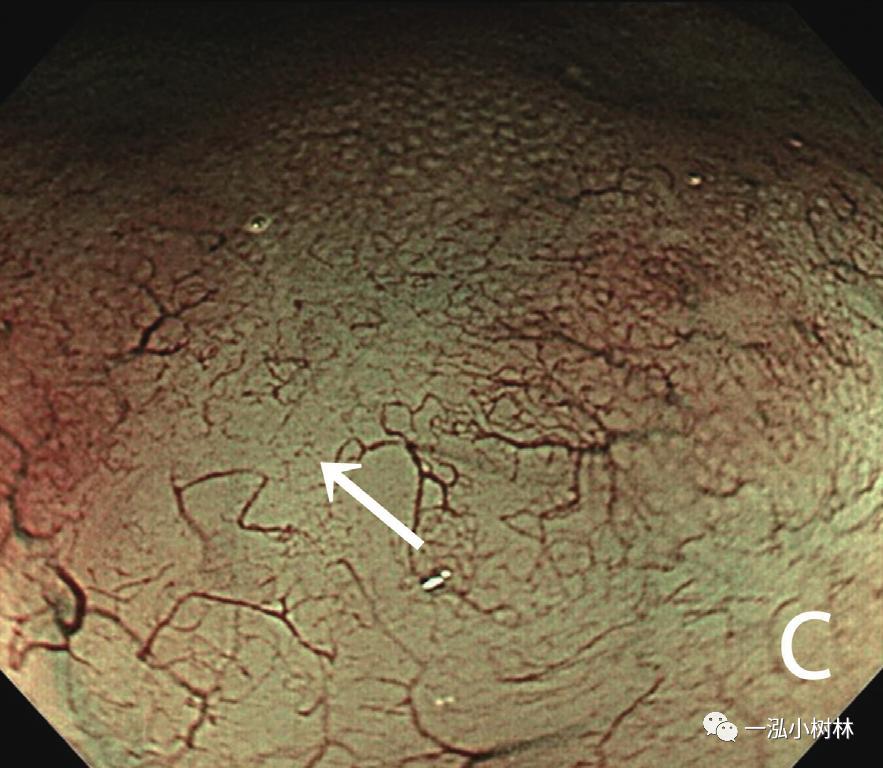

内镜检查(图1):胃黏膜整体粗糙、弥漫性隆起,易出血。在胃体下部、胃窦部黏膜的粗糙明显,散在小隆起,一部分也发现了较大的隆起性变化。ME-NBI观察即使残留着接近正常的腺管,表面微细结构的消失也很明显,在褪色区域也发现了血管的扩张和蛇行、腺管结构的紊乱。

图1c ME-NBI 胃体下部褪色区域中不能识别白区,微小血管的密度降低很明显(箭头)。(问题:NBI放大表现如何与MALT淋巴瘤鉴别)